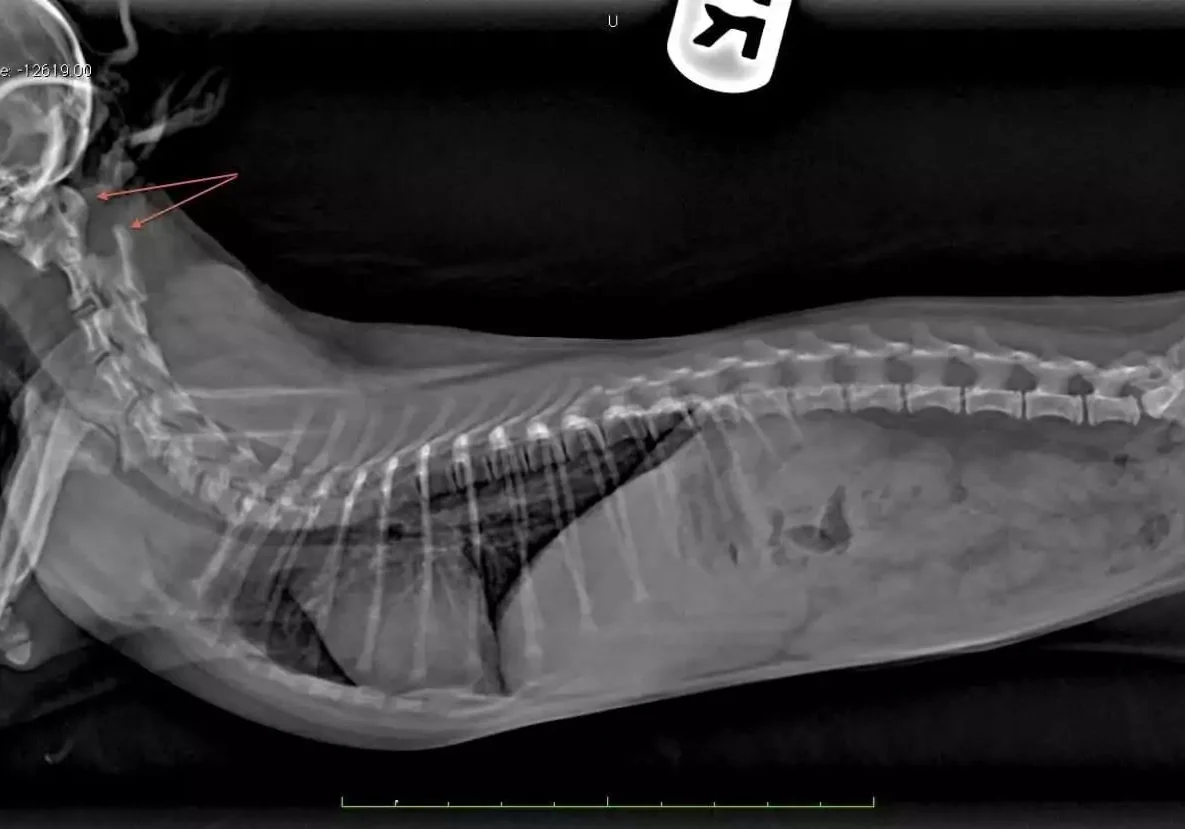

Radiographs of her neck by her veterinarian showed a condition called atlantoaxial subluxation.

Below are radiographs of Gracie before and after her neck splint was placed. Note the large space between the first two bones in Gracie’s neck prior to reduction.

Referring radiographs showing atlantoaxial subluxation. Note the increased space between C1 and C2.